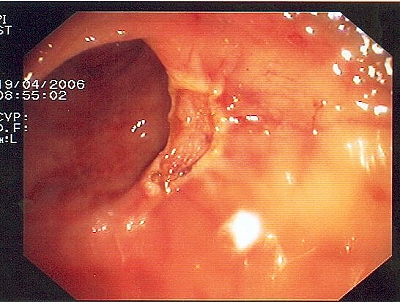

Gut sichtbarer Blutstrahl nach Abtragung eines Polypen

Sichere Blutstillung durch einen Metallclip